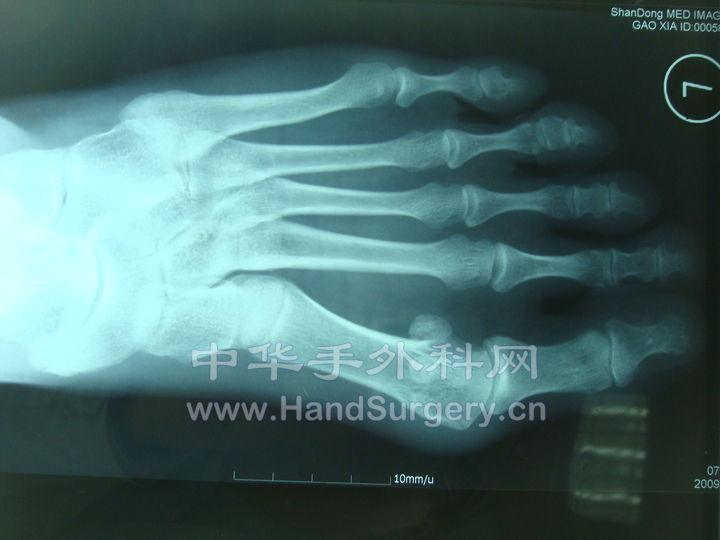

这是一个拇外翻的线片。scarf+Akin术前,术后。